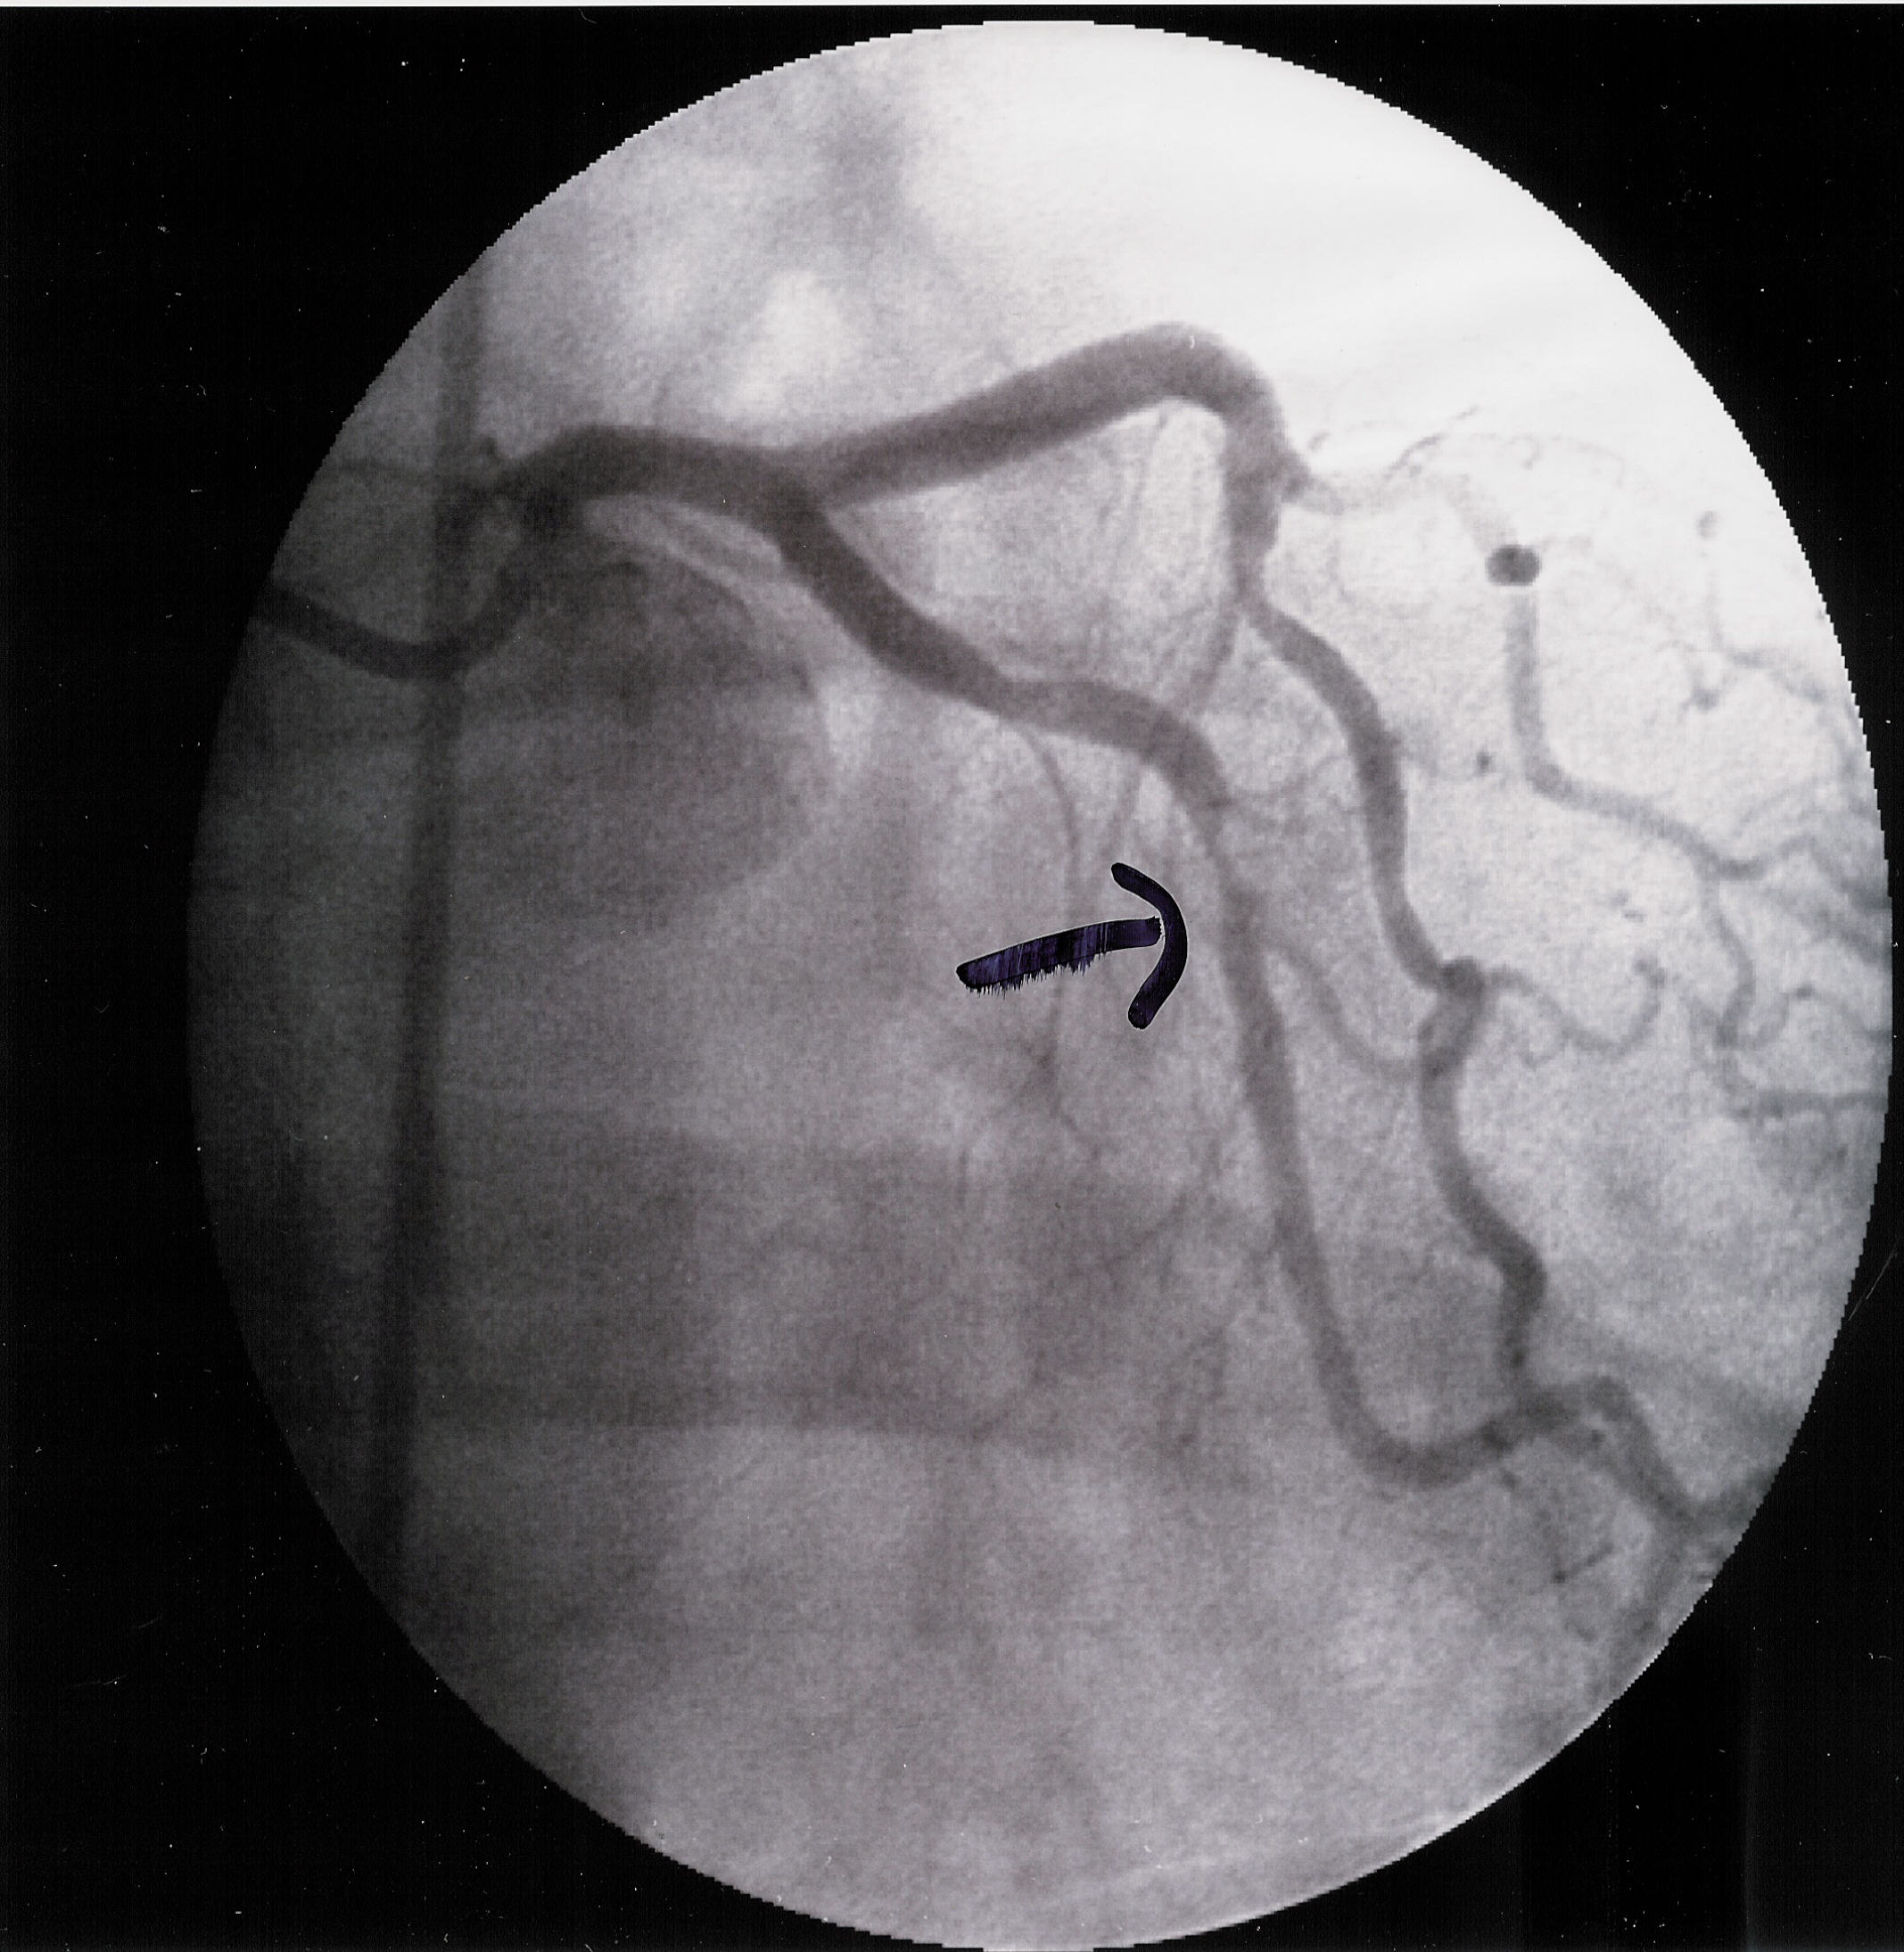

My heart attack and what happened

Friday Morning at 11:30 they took me into the operating

theater and started there stuff. and here is the result below. It appears to

be the oxygen veins that supply oxygen to the heart. The doc told me I would

Before